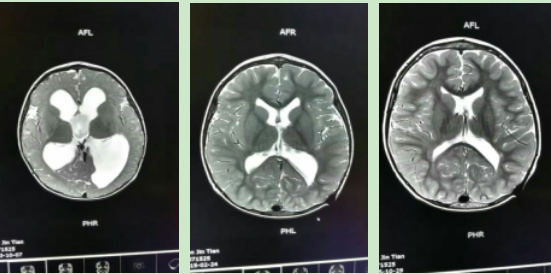

小孩发生脑积水有多种原因,如由缺氧缺血性脑损伤导致脑白质损伤所致脑室扩大,其影像检查结果在很大程度上与脑积水相似,但是其后果相比其他病因更加严重,预后更差。我们经过仔细的分析、鉴别,明确告知家属,小孩脑积水不是由脑白质减少所致,经过脑积水引流术等治疗恢复健康的可能性很大,而且越早治疗效果越好。按照我们的建议,家长立即把病孩送到上海进行了脑积水引流术,并严格按照儿童保健科医生的指导进行了两年专业按摩治疗,病情逐渐好转,经过评估后孩子的运动及智力达到了同龄儿水平。

孩子大脑的磁共振图片(分别为治疗前、治疗中及最近一次检查)